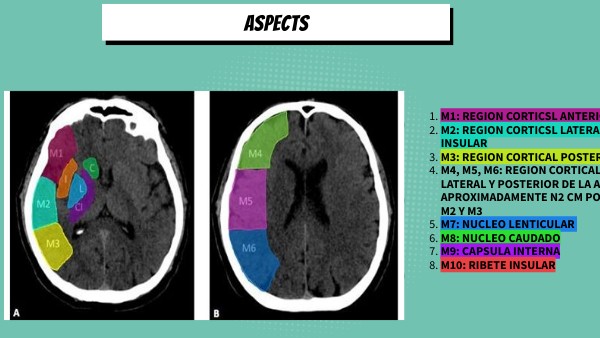

ASPECTS

1. M1: REGION CORTICSL ANTERIOR DE LA ACM

2. M2: REGION CORTICSL LATERAL DELN RIBETE INSULAR

3. M3: REGION CORTICAL POSTERIOR DE LA ACM

4. M4, M5, M6: REGION CORTICAL ANTERIIOR, LATERAL Y POSTERIOR DE LA ACM APROXIMADAMENTE N2 CM POR ENCIMA DE M1, M2 Y M3

5. M7: NUCLEO LENTICULAR

6. M8: NUCLEO CAUDADO

7. M9: CAPSULA INTERNA

8. M10: RIBETE INSULAR